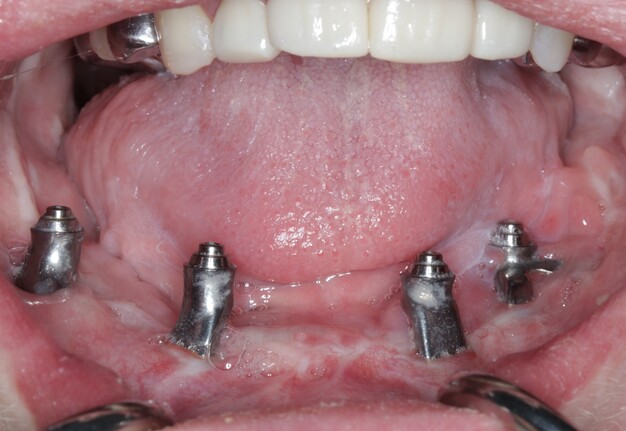

A custom occlusal splint confirmed mount and prosthetic space. The site was closed with resorbable sutures intraorally and plain gut at trocar sites. Recovery was uneventful, and the patient progressed to prosthetic rehabilitation (Figs 9 and 10).

The existing prototype was removed using an extra-short multi-unit abutment (MUA) prosthetic screwdriver (BioHorizons). The patient shifted his mandible laterally to permit access to posterior screw channels (Fig 11).

The refined prototype was rescanned on the back-pour cast, and a definitive monolithic implant supported fixed zirconia prosthesis was fabricated and successfully delivered (Figs 16 and 17).